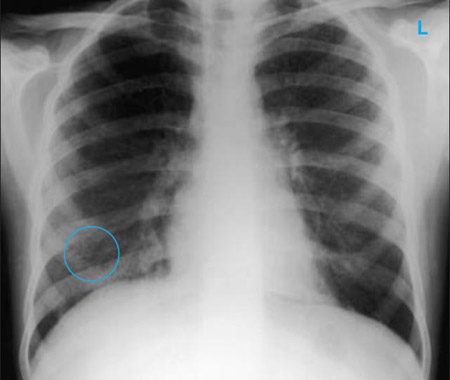

Chest x-ray showing multiple discrete nodules throughout both lungs (one of which is circled) in a patient with miliary tuberculosis

E. Dick, Student BMJ. 2001;9:10-12